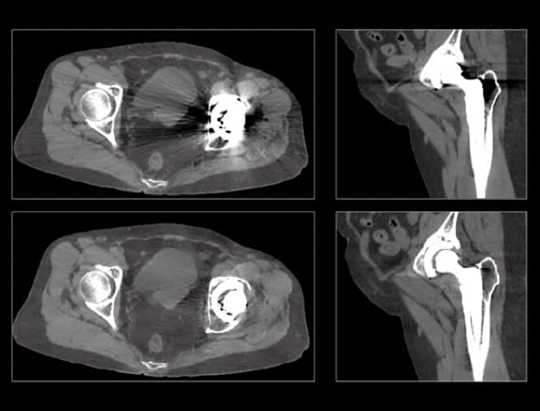

The large 24 cm axial digital PET field of view (FOV) provides exceptional image quality with 2.9 mm NEMA resolution that improves quantitative accuracy and small lesion detectability.

This fully configured 80-slice diagnostic CT produces high image quality with low radiation dose that can be used as a standalone or back-up CT for Radiology procedures.